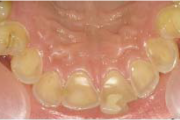

Hambad